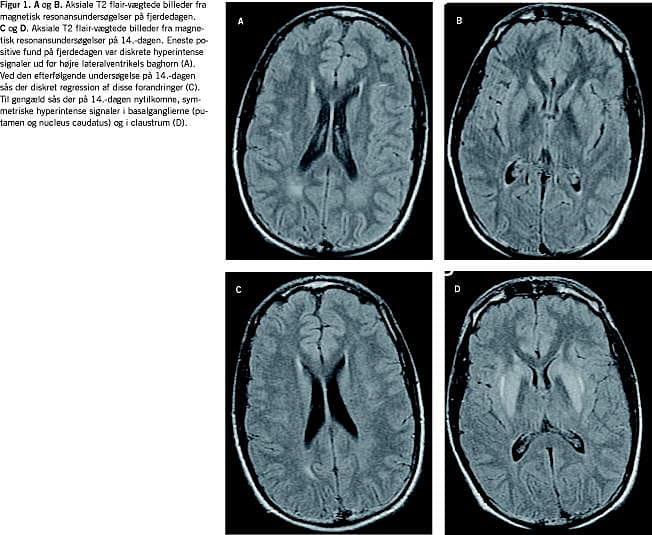

Efter to døgn var patienten cerebralt klar, men svarede stadig med latenstid. En magnetisk resonans (MR)-skanning fire dage efter indlæggelsen viste diskrete uspecifikke forandringer i den hvide substans ud for højre lateralventrikels baghorn (Figur 1 A+B).

Ti dage efter indlæggelsen var patienten motorisk urolig, dysartrisk, grædende, savlende, hypotensiv, havde sitrende trækninger i ansigtet og synkebesvær. Dosis af glukokortikoid var da 20 mg × 2 dagligt og P-Na var 140 mM. Resultaterne af et elektroencefalogram var foreneligt med diffus encefalopati, og patienten blev overflyttet til neurologisk regi på mistanke om ODS. Her fandt man påvirkning af kranienerverne VII, IX, X og XII samt ekstrapyramidal påvirkning med rigiditet, bradykinesi, amimisk ansigt og ændret kropsholdning. Der var ingen pyramidebanesymptomer. En MR-skanning 14 dage efter indlæggelsen viste symmetriske forandringer i basalganglierne, hvilket er foreneligt med ekstrapontin myelinolyse (EPM) (Figur 1 C+D). Forandringerne ud for baghornet var uændrede. Adrenomyeloneuropati, Wilsons sygdom og neurolues blev udelukket. Patienten blev behandlet med antiparkinsonmedicin med effekt på de ekstrapyramidale symptomer og blev efter genoptræning på Hammel Neurocenter udskrevet efter eget ønske 35 dage efter indlæggelsen. Ved udskrivelsen persisterede der kun let monoton tale, en højresidig primær hviletremor og en moderat afficeret diadokokinese.